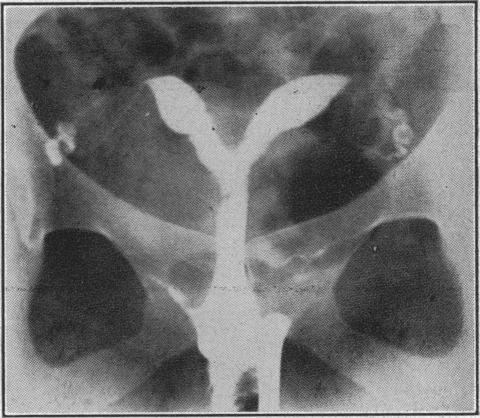

Congenital abnormalities of the uterus and pregnancy.

https://cdn.ncbi.nlm.nih.gov/pmc/blobs/ebe1/1979618/e85ff3696382/brmedj03207-0022-a.jpg